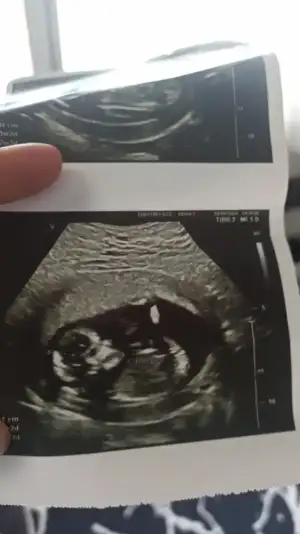

D Dantewn hello ben geldim. 11+3 ultrason fotoğraflarım burada. Doktor emin olamadı nub sanki çıkık ama tam açısında da değil zaten 12 den önce erken dedi ama diğer açıda da eğer o yatay olan nub ise birinci ultrasonla alakası yok. Sence nedir bu küçük ördek?